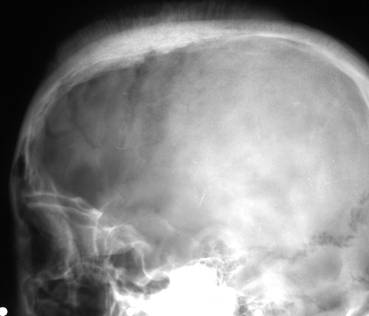

Radiografic se pot constata:

Fisuri craniene

Fracturi nedenivelate (liniare, cominutive, disjunctii suturare, f 656b14g racturi-disjunctie);

Fracturi denivelate (evulzive, cu extruzie si depresive, cu infundare);

Fracturi complexe (cranio-otice, cranio-sinusale, etc).

Fig. 98 – Fractura de bolta caraniana fronto-parietala stanga si parieto-temporo-occipitala dreapta